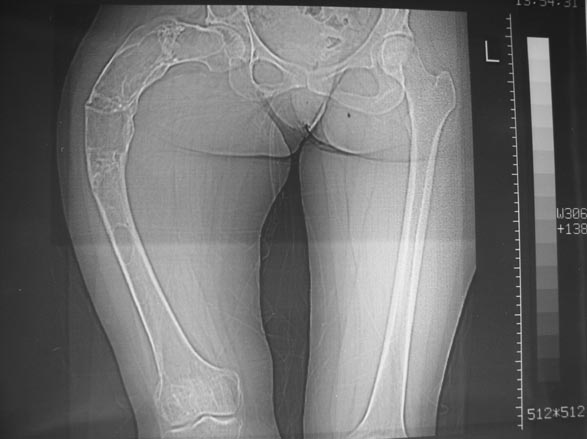

Шахсувар Асадов 18 Ноябрь 2009, 16:04

Беспокою вас на счет деформации правой бедренной кости после патологических переломов.

Мне 15 лет. Случилось все когда мне было 10 лет 26.12.04 я был дзю-доистом и в одном из соревнований сломалась правая бедренная кость. перелом был внутренний со смещением. Взяли и сделали операцию, поставили пластинку и тем самым заложили инфекцию. Потом кость начала гнить и сняв пластинку, через три месяца поставили аппарат Илизарова. Он отлежал месяцев шесть с мая по сентябрь. и когда снимали кость снова отошла. то есть сломалась. по правую сторону бедра были дырки из которых шел гной и которые закрылись уже в 2006 году. далее поправив поставили в гипс который остался больше шести месяцев. прошли месяцы и все вроде было в порядке. потом опять сломалась изза простейшей причины в августе 2006 года. опять поставили в гипс. прошло время и снова когда спускался с бордюра сломалась в четвертый на данный момент последний раз 23 мая 2008 года. с тех пор кроме патологических разломов кости тревожила еще одна проблема. та самая деформация. только со временем она становиться еще сильней.

Прошу вас помочь в ситуации. живу в Баку, Азербайджане. Здешние врачи говорят что можно исправить ТОЛЬКО Илизаровским аппаратом. что меня сильно беспокоит так как он уже у меня был.